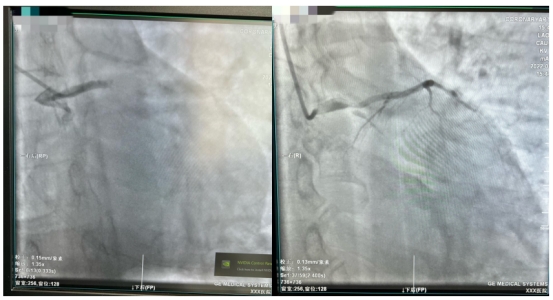

在从江北患者家中送往医院的路上,急救医生就将心电图发到哈医大一院胸痛中心微信群里,医生会诊后即启动导管室做好手术准备。到医院后,在无核酸结果的情况下,张先生直接被推进急诊负一层的负压导管室,而此时张先生已有心率减慢、血压下降状况。经紧急冠脉造影后发现,冠状动脉左主干尾部被一个大血栓阻塞,远端完全闭塞。在非常凶险情况下,医师立即为他植入IABP(主动脉内球囊反搏装置)以维持血压,并在IABP保护下行冠脉内血栓抽吸和支架植入术,几分钟后张先生的血管被开通,命总算被救了回来。患者入医院大门到导丝通过病变时间仅为30分钟,而从急救医生接触患者到导丝通过病变时间也仅为50余分钟。

到达医院后,刘先生在无核酸报告的情况下被推到负压导管室,紧急造影显示为左主干尾部90%狭窄,前降支近端90%狭窄并血栓影,回旋支完全闭塞。刘先生在IABP保护下成功进行了左主干血管开通,入医院大门到导丝通过病变时间仅为29分钟。